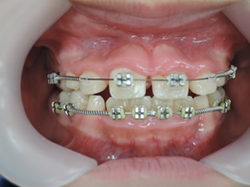

☆上顎から矯正装置を装着していきます。

☆上顎の歯が揃ってから、下額に矯正装置(ブラケット)を装着します。

☆終了時(1年6ヶ月)